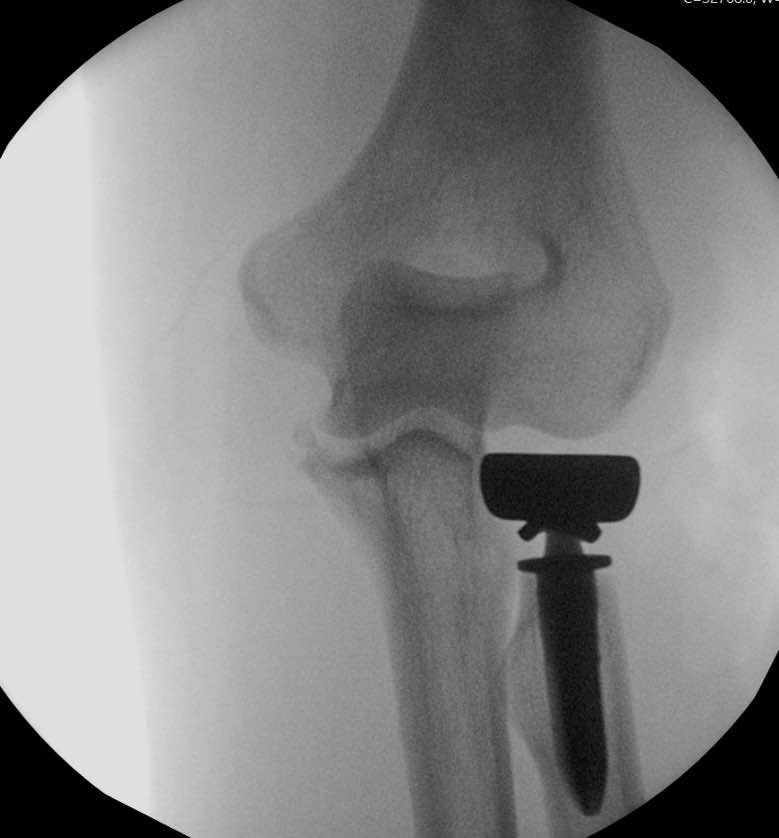

- Fixation or arthroplasty of the radial head

Most terrible triad injuries require surgical management to restore the functionality of your elbow. Surgery involves addressing all the injury components in your elbow. These may include fixation or replacement of the radial head, fixation or suturing of the coronoid and repair of the avulsed ligaments of your elbow.